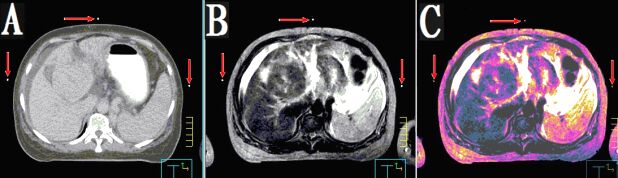

本產(chǎn)品主要適用于不同模態(tài)圖像引導(dǎo)下放療時(shí)定位,定點(diǎn)經(jīng)皮穿刺活檢或積液抽吸引流,不同模態(tài)間圖像融合控制點(diǎn)配準(zhǔn)等。

2.??多角度掃描小球,圖像均為高亮度圓點(diǎn)狀,無放置角度限制。

3.??同一定位貼,在多種模態(tài)掃描下成像均能顯示為點(diǎn)狀,可用作圖像融合的共同配準(zhǔn)控制點(diǎn),大小、位置一致,方便全身或軀段臟器異機(jī)圖像融合,精度高,易開展新的臨床應(yīng)用。

CT和MR通用型:具有同一個(gè)定位球在CT掃描高密度、MR常規(guī)掃描高信號(hào)的特點(diǎn),主要用于

CT/MR圖像融合,更換掃描設(shè)備,不需要更換標(biāo)記點(diǎn)。型號(hào)MK⊙CT/MR,每盒三貼;